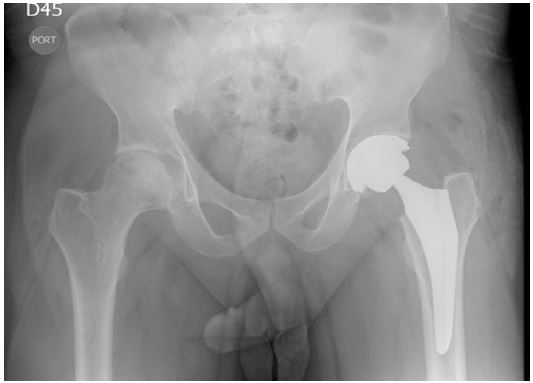

A primary total hip prosthesis with ceramic-polyethylen was used, with postoperative radiography with adequate position of the components and restoration of the offset (Figure 4).

Figure 4: Postoperative Anterior-posterior hip X-ray showing left total hip artrhoplasty with ceramic-polyethylene bear surface.